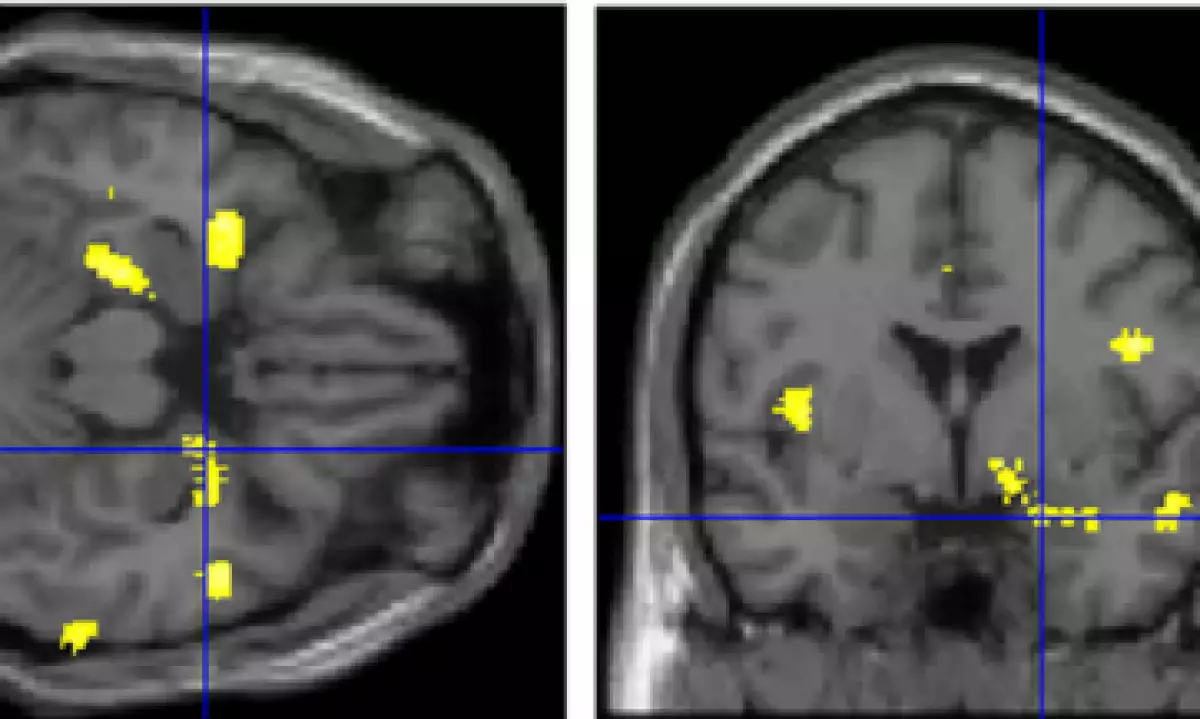

En pocas palabras, parece que la respuesta es sí. El neurocientífico Hikaru Takeuchi, de la Universidad de Tohoku, y sus colegas notaron que dos regiones del cerebro que contienen las actitudes sexistas tienen grados diferentes de densidad de la materia gris (lo que indica básicamente la cantidad de neuronas que hay en una región determinada) en comparación con las personas que dicen que creen en la igualdad de género (en su estudio no se habla de las creencias sexistas subconscientes). Es más, estas diferencias neurales tienen una relación directa con las características psicológicas que podrían explicar algunas de las creencias sexistas de la gente.

El equipo de Takeuchi descubrió que los puntajes bajos en la escala SRE (tener creencias más sexistas o discriminadoras por género) tienden a estar relacionados, tanto en hombres como en mujeres, con una densidad mayor en la materia gris de la corteza cingulada posterior, una región del cerebro relacionada con el procesamiento de cosas como la ira, el miedo y el dolor; también hay relación con la densidad reducida en la amígdala derecha, otra de las regiones del cerebro muy importantes para las emociones, particularmente el miedo.

En el contexto actual, cuando menos podemos buscar pistas en otros marcadores psicológicos que los investigadores recabaron. Por ejemplo, descubrieron que la presencia de más materia gris en la cingulada posterior no solo se relaciona con las creencias sexistas, sino con la mayor propensión a la ira y a la hostilidad (aunque a un grado muy bajo) y con una personalidad competitiva.

Por otro lado, la presencia de un nivel menor de materia gris en la amígdala se relacionó ligeramente con los puntajes más altos de neurosis (en mujeres) y con una mayor propensión a la depresión. Algunas investigaciones anteriores relevantes revelaron que el volumen reducido en la amígdala se relaciona con el estrés, la ansiedad y la depresión (aunque cabe señalar que hay otras investigaciones en las que se relaciona el agrandamiento de la amígdala con problemas emocionales… ¡desafortunadamente, las neurociencias rara vez son sencillas!).